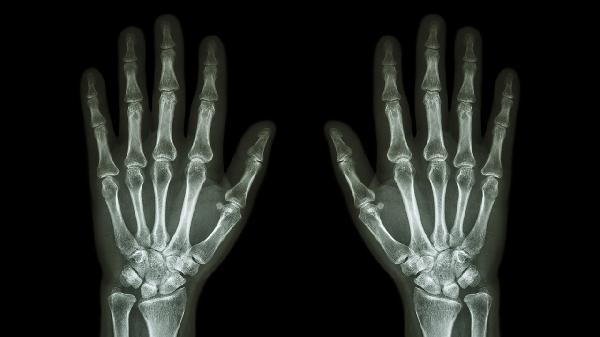

手指关节褶皱处发黑是怎么回事

手指关节褶皱处发黑可能与色素沉着、摩擦刺激、真菌感染、湿疹或黑棘皮病等因素有关。皮肤长期受压或反复摩擦会导致局部角质增厚,真菌感染可能伴随脱屑瘙痒,内分泌紊乱可能诱发黑棘皮病的特征性改变。